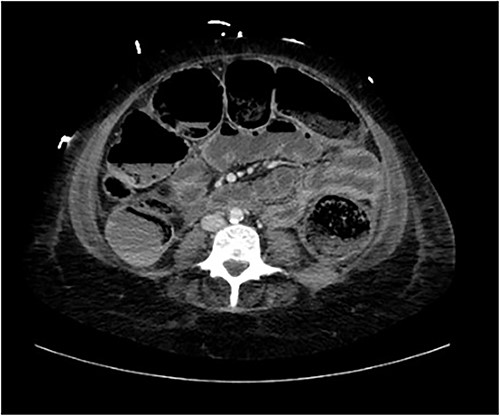

A provisional diagnosis of a ‘bowel obstruction’ was made and she was admitted to hospital for conservative management with nasogastric drainage, intravenous hydration, and aperients. Over the following 24 h, her abdominal pain remained severe and further surgical review was sought. At this stage she exhibited a distended, firm, exquisitely tender abdomen. A repeat CT at this time once again demonstrated faecal loading, normal bowel wall enhancement, and no perforation (Figs 1 and 2). At this stage she was fasted and consented for an exploratory laparotomy under general anaesthesia. She proceeded to theatre after reversal of her INR with prothrombinex and vitamin K.

Coronal view of CT abdomen demonstrating normal large bowel wall enhancement with faecal loading.